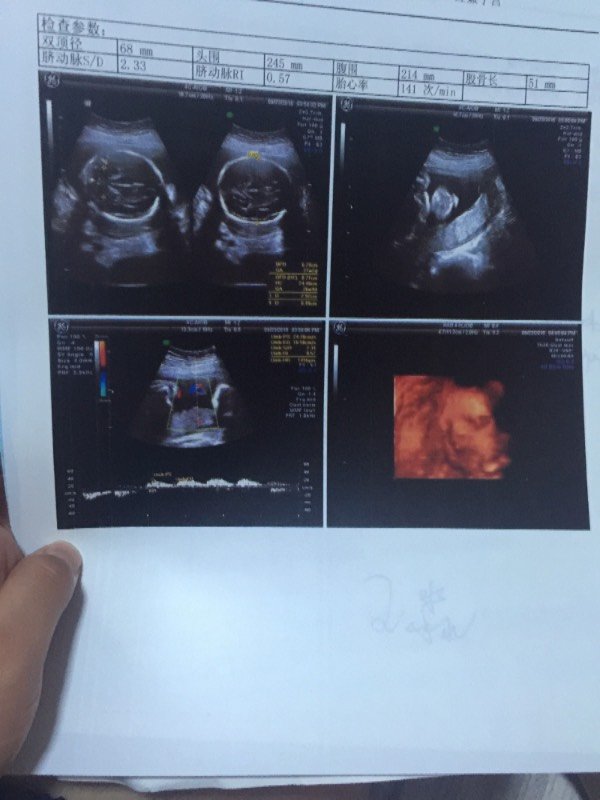

大家能帮我看看我怀孕六个月了,根据这些数据能大概判断出男女吗?谢谢 我只是好奇 有经验的人请进 点击展开 匿名用户 2015-09-23 21:10 为您推荐: 其他回答 照片明显太模糊了,根本就看不清楚。 (看看大腿根里有没有“杀气”就好了,但是照片太模糊了。) 问问医生就好了,医生一定会懂的,只是不会随便说,隐秘的问就好了。 实在不行就给红包。没什么不能给的! 汤兴昌_LdhU 2015-09-23 21:20 生男生女都一样 匿名用户 2015-09-23 21:19 恭喜你是男的 匿名用户 2015-09-23 21:18 是个男孩。 匿名用户 2015-09-23 21:14 相关问题 听说唐筛数据能看出男女 麻烦懂的帮我看看 这是第一胎宝贝 就是好奇 请问这个检查能看的出来男女吗?我不是重男轻女,我就是好奇,希望懂行的可以帮我看看,谢谢! 请问这个检查能看的出来男女吗?我不是重男轻女,我就是好奇,希望懂行的可以帮我看看,谢谢…